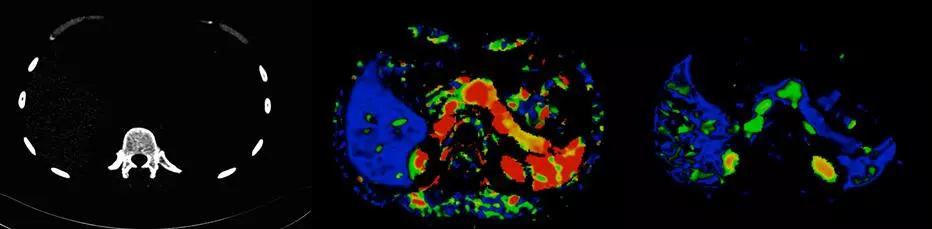

Force CT突破了探測器的限制,實現業內最寬的80cm大范圍、5倍于寬體CT探測器覆蓋范圍,真正實現全臟器灌注,同時具備低70KV灌注成像技術,可以做到全器管灌注的輻射劑量只相當于一次CT平掃。

△70 kV胰腺神經內分泌腫瘤灌注